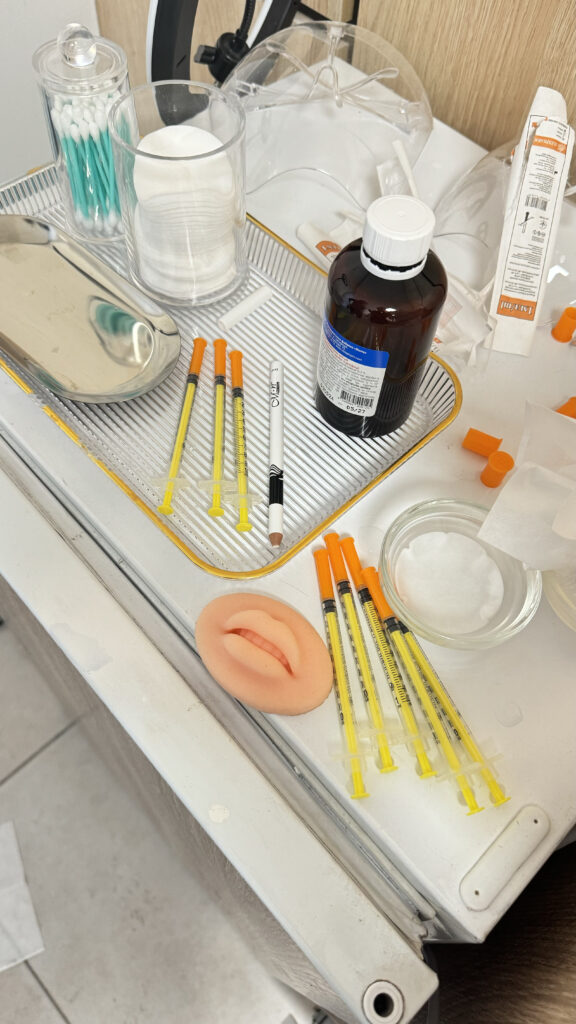

MG CLINIC — це простір, де ваша краса починається зі здоров’я. Ми пропонуємо повний спектр послуг дерматовенерології (лікування дерматозів, акне, розацеа, діагностика та видалення новоутворень), трихології, доглядової, апаратної та ін’єкційної косметології.

MG CLINIC — це простір, де ваша краса починається зі здоров’я. Ми пропонуємо повний спектр послуг дерматовенерології (лікування дерматозів, акне, розацеа, діагностика та видалення новоутворень), трихології, доглядової, апаратної та ін’єкційної косметології.

ОБЛАДНАННЯ клініки